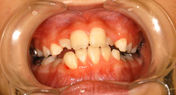

下顎前突(かがくぜんとつ)・受け口

主訴:受け口・前歯部交叉咬合

年齢:7y2m

診断:上顎劣成長による骨格性下顎前突

装置・期間:

第一期治療 上顎拡大+上顎前方牽引装置(クアッドヘリックス+フェイシャルマスク)+バイヘリックス+セクショナルアーチ 6年7カ月間(7y5m~14y0m)

第二期治療 上下顎マルチブラケット装置 3年5カ月間(16y2m~19y7m)

保定 上下顎保定装置 2年間以上

治療費:第一期治療 矯正基本料400,000円+処置料3,000~6,000円×40回(別途消費税)

第二期治療 矯正基本料400,000円+クリアブラケット代30,000円+処置料3,000~6,000円×37回(別途消費税)

保定装置料 55,000円(別途消費税)